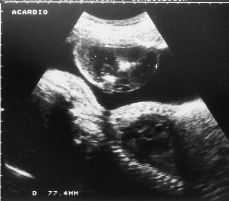

En la semana 26,6 de gestación la paciente es remitida al hospital para diagnóstico diferencial de una masa de unos 40-50 mm que aparece en contacto con el polo inferior de la placenta. La exploración ecográfica es de feto único en podálica con desarrollo acorde con amenorrea, LA abundante dentro de la normalidad. En contacto y como adyacente al borde inferior de la placenta hay una masa de 40 x77 mm, en la que se observan estructuras óseas fetales que sugieren la presencia de un feto acardio-anencéfalo (Fig. 1).

Figura 1.Ecografía prenatal que muestra un corte longitudinal del feto vivo. Dependiente de la pared uterina anterior hay una masa heterogénea, muy bien delimitada, que hace impronta en la cavidad amniótica. Esta imagen muestra dos áreas muy refringentes que se interpretan como estructuras óseas del feto acardio.